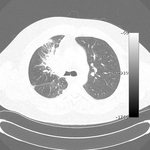

Злокачественная эндобронхиальная обструкция на мультидетекторной КТ: легочное окно, демонстрирующее злокачественную обструкцию правого главного бронха

Из коллекций Хосе Фернандо Сантакруза, дипломированного врача, члена Американской коллегии специалистов в области торакальной медицины, DAABIP, и Эрика Фолка, дипломированного врача, магистра наук; используется с разрешения